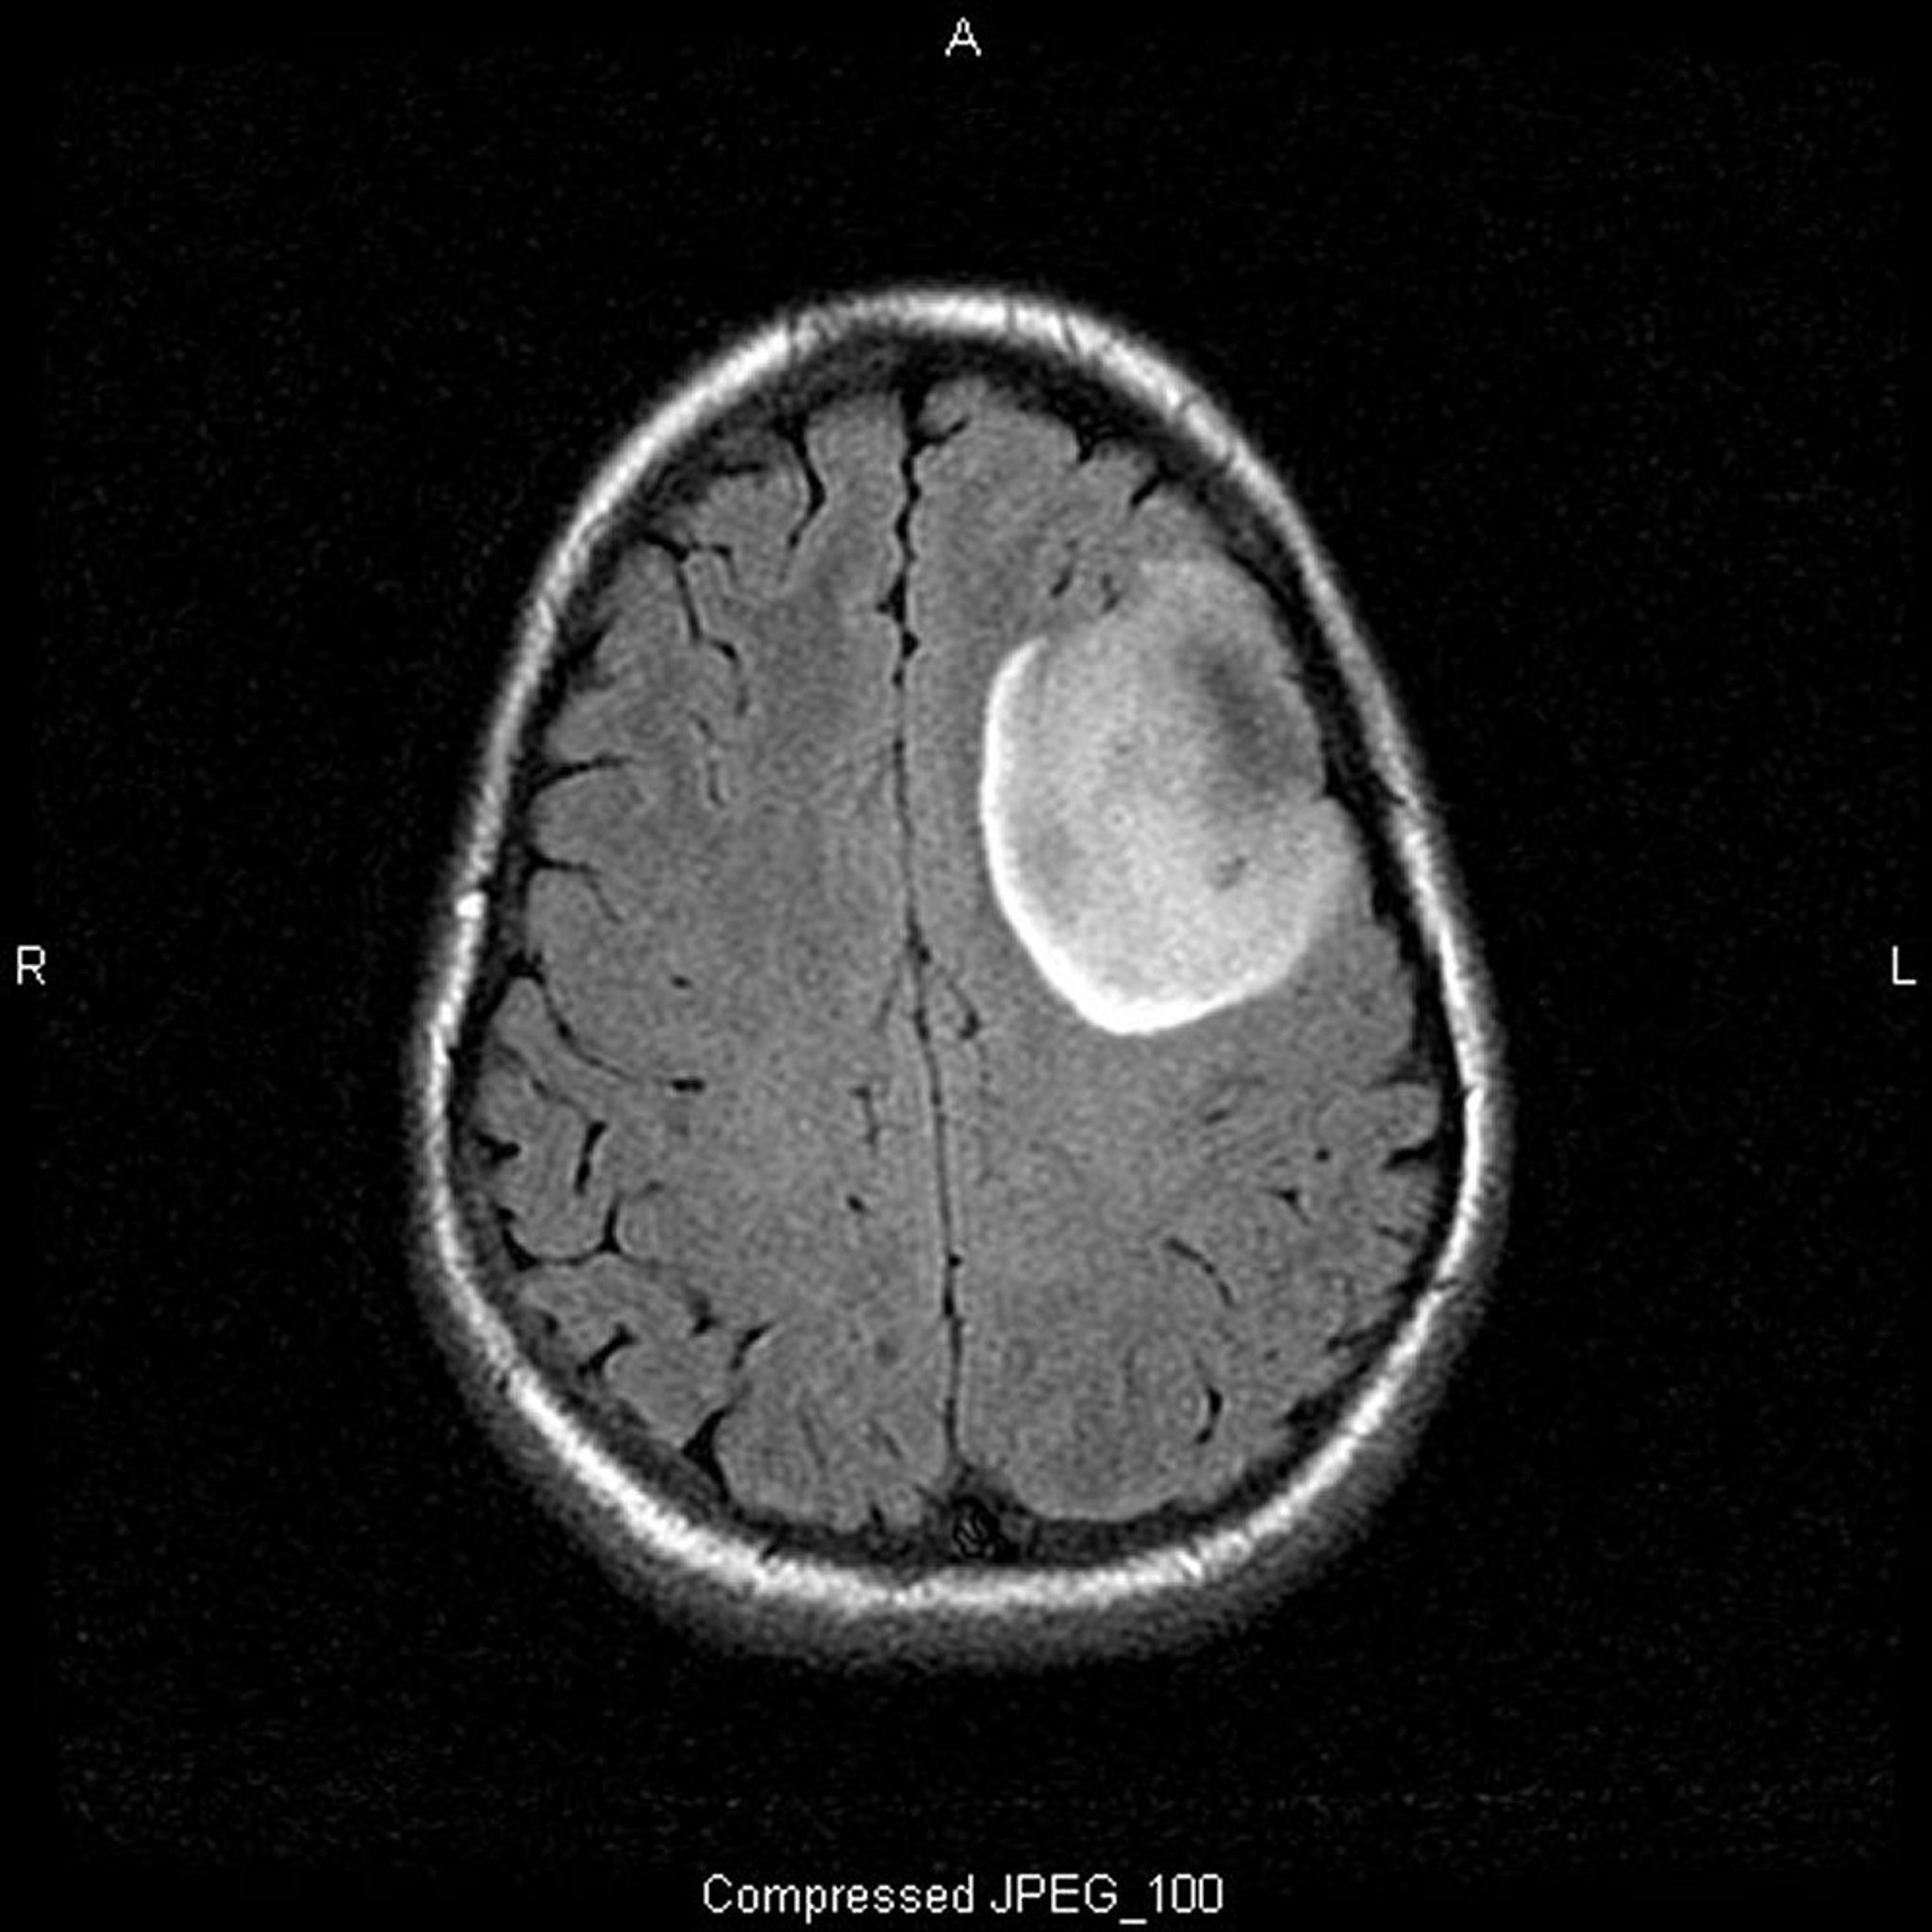

U thần kinh đệm ít nhánh, mức độ thấp

Phim chụp MRI T2-FLAIR (chuỗi xung xóa tín hiệu các dịch) này cho thấy một tín hiệu màu trắng, có thể cho biết một khối hoặc phù nề. Tín hiệu phía trước bên trái được phân định rõ ràng, gợi ý một khối lớn. Sử dụng chất cản quang không làm ngấm thuốc vùng đó. Đó là u thần kinh đệm ít nhánh mức độ thấp (độ II).

Hình ảnh do bác sĩ William R. Shapiro cung cấp